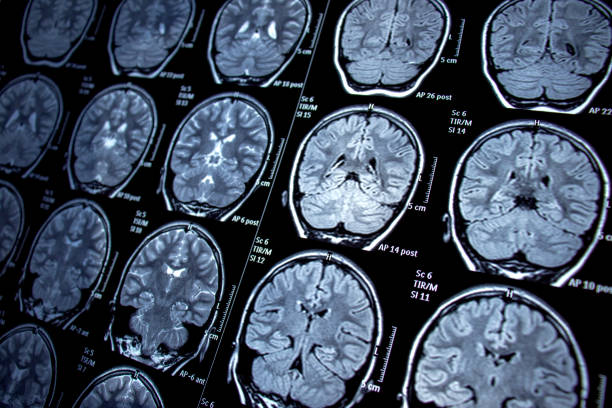

- 技術助力定位:隨著功能性磁共振成像(fMRI)等先進成像技術的發展,外科醫生能夠定位癲癇區域,并確定大腦相應區域手術可能導致的術后缺陷。

- 預后較好情況:MRI 上具有電臨床一致的結構性病變的患者預后最好,60% 至 70% 的病例癲癇發作能減少。

- 預后較差情況:患有顳葉外病灶、局灶性至雙側強直陣攣性癲癇、影像學正常、精神合并癥以及學習障礙的患者通常手術成功率較低。

EEG記錄顯示θ活動和尖峰密度降低。6個月后,8名患者 (40%) 不再癲癇發作。隨時間推移,記憶評分顯著增加。BMMC自體移植用于治療顳葉癲癇是可行且安全的。這項新研究中實現的癲癇控制支持干細胞移植對MTLE-HS患者的治療潛力。